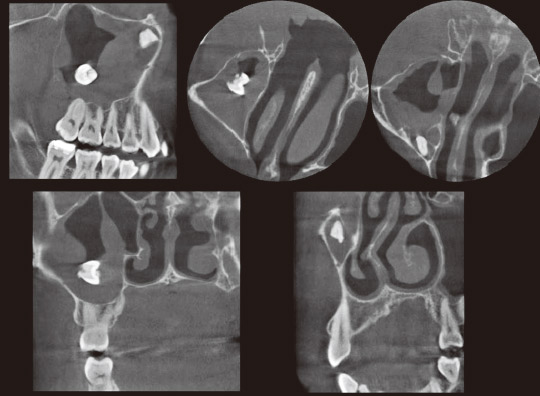

治療開始時のデンタルX線写真では上顎左側7近心にX線透過像がみられた。6にはインレー修復がされており、2次カリエスを疑う以外に問題になる所見はみられなかった。CTを撮影したところ、矢状断では7近心のX線透過像は6の歯根中隔にまで拡がっていた。上顎左側洞粘膜は肥厚していた(図9)。冠状断と軸断では7近心根近心面からX線透過像は6の歯根中隔をとおり、6近心遠心根の間まで拡がっていた。6近遠心根中央の皮質骨は消失していた。

根管治療が進むにつれX線透過像が存在した部位に海綿骨様の構造がみられるようになり、頰側の皮質骨が改善していた(図10)。

この症例を通じて、瘻孔は時として複雑な場合があり、原因歯を特定することが難しい症例では歯科用CTが有効であることを経験した。

図9 左上:治療開始時デンタルX線写真。右上:治療開始時CT写真(矢状断)。下左:根充後CT写真(矢状断)。下右:治療後6ヵ月CT写真(矢状断)。

図10 CT写真(冠状断と軸断)。左より術前、根充時、治療後6ヵ月。軸断は6の近心根と遠心根の中央(赤線)を示す。